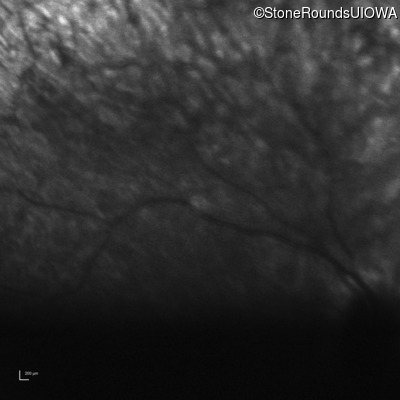

Infrared Fundus Photograph - Left - Hand Motion 6" sc

Exemplar